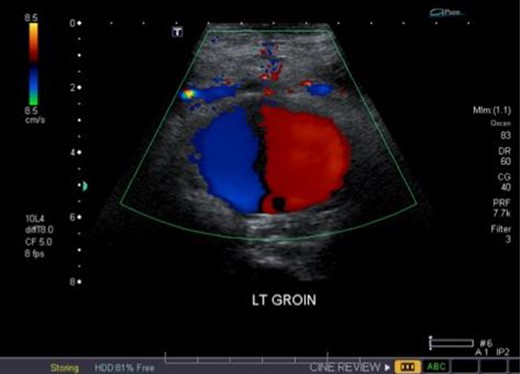

Duplex ultrasound overlying the left groin demonstrating bidirectional flow in the pseudoaneurysm (i.e. ‘yin-yang’ sign).

Unfortunately, due to increasing pain and difficulty weight-bearing, she presented to the emergency room on POD33. She was found to have new left thigh swelling and pain. Deep vein thrombosis (DVT) was ruled out with duplex ultrasound; however, a large left DFA pseudoaneurysm measuring 5.6 cm in length with a neck of 0.4 cm was visualized (Fig. 2). Computed tomography (CT) imaging confirmed a left DFA branch pseudoaneurysm with active extravasation, adjacent to a free-floating osseous fragment, associated with a large thigh hematoma (Fig. 3). In consultation with hematology, her apixaban was not reversed.